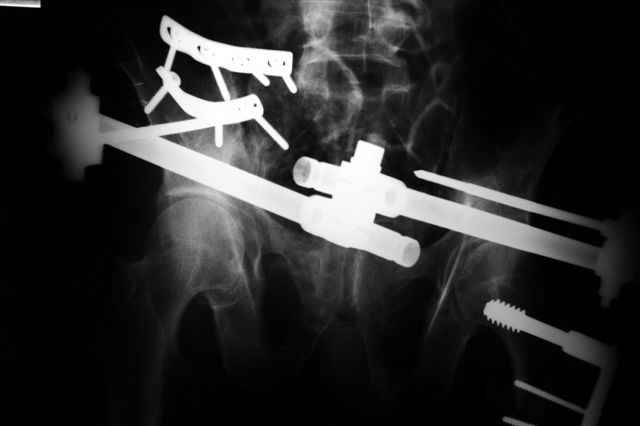

В приложении послеоперационные картинки.

При поступлении передняя рама (фиксация просто за гребни), соединенная с мыщелками бедра.

После стабилизации состояния перевернуть больного на живот или на бок, пару винтов закрыто через заднюю ость трансфрактурно в крыло слева (если не нравится стояние фрагмента, можно предворительно задним латеральным доступом отрепонировать), справа не очень понятно куда идет перелом крыла, но если фиксировать, то пластиной по наружной стороне.

Интраоперационно у меня не возникло сомнений , что Шанцы прошли через КП сочленения: сначала провёл Шанц справа при открытой ране после фиксации КП

сочленения пластинами и контролем ЭОПа инлет и аутлет проекциях, определившись с углом введения винта. затем слева - под Рг-контролем, отступив на 2 см латеральнее нижней ости, чтобы не провалиться в таз.